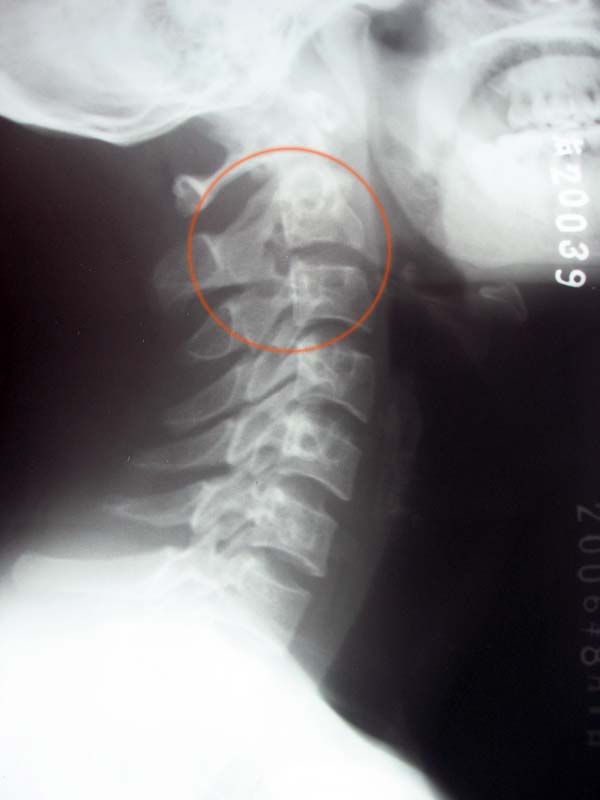

第三颈椎上关节突似分离,可见小三角形骨影与椎板分开,其边缘可见硬化,未见骨质破坏改变.考虑 解剖变异. ---c3上关节突永存骨垢.

侧位片所示圈子内我认为还是投照体位所致,各解剖结构还是完好存在.正位片示环椎双侧块圆孔样改变,应为变异,是侧方骨桥形成

第三颈椎上关节突似分离,可见小三角形骨影与椎板分开,其边缘可见硬化,未见骨质破坏改变.考虑 解剖变异可能. ---c3上关节突永存骨垢.建议ct检查

生理曲度可~擐枢锥双侧间隙大小不同~c3上关节突 骨赘形成~

我看不是解剖变异,局部有骨质破坏,建议ct检查

解剖变异,c3上关节突永存骨垢.建议ct检查

好象附件见"鼠咬样"改变.如ct能发现椎旁脓肿,应考虑tb.